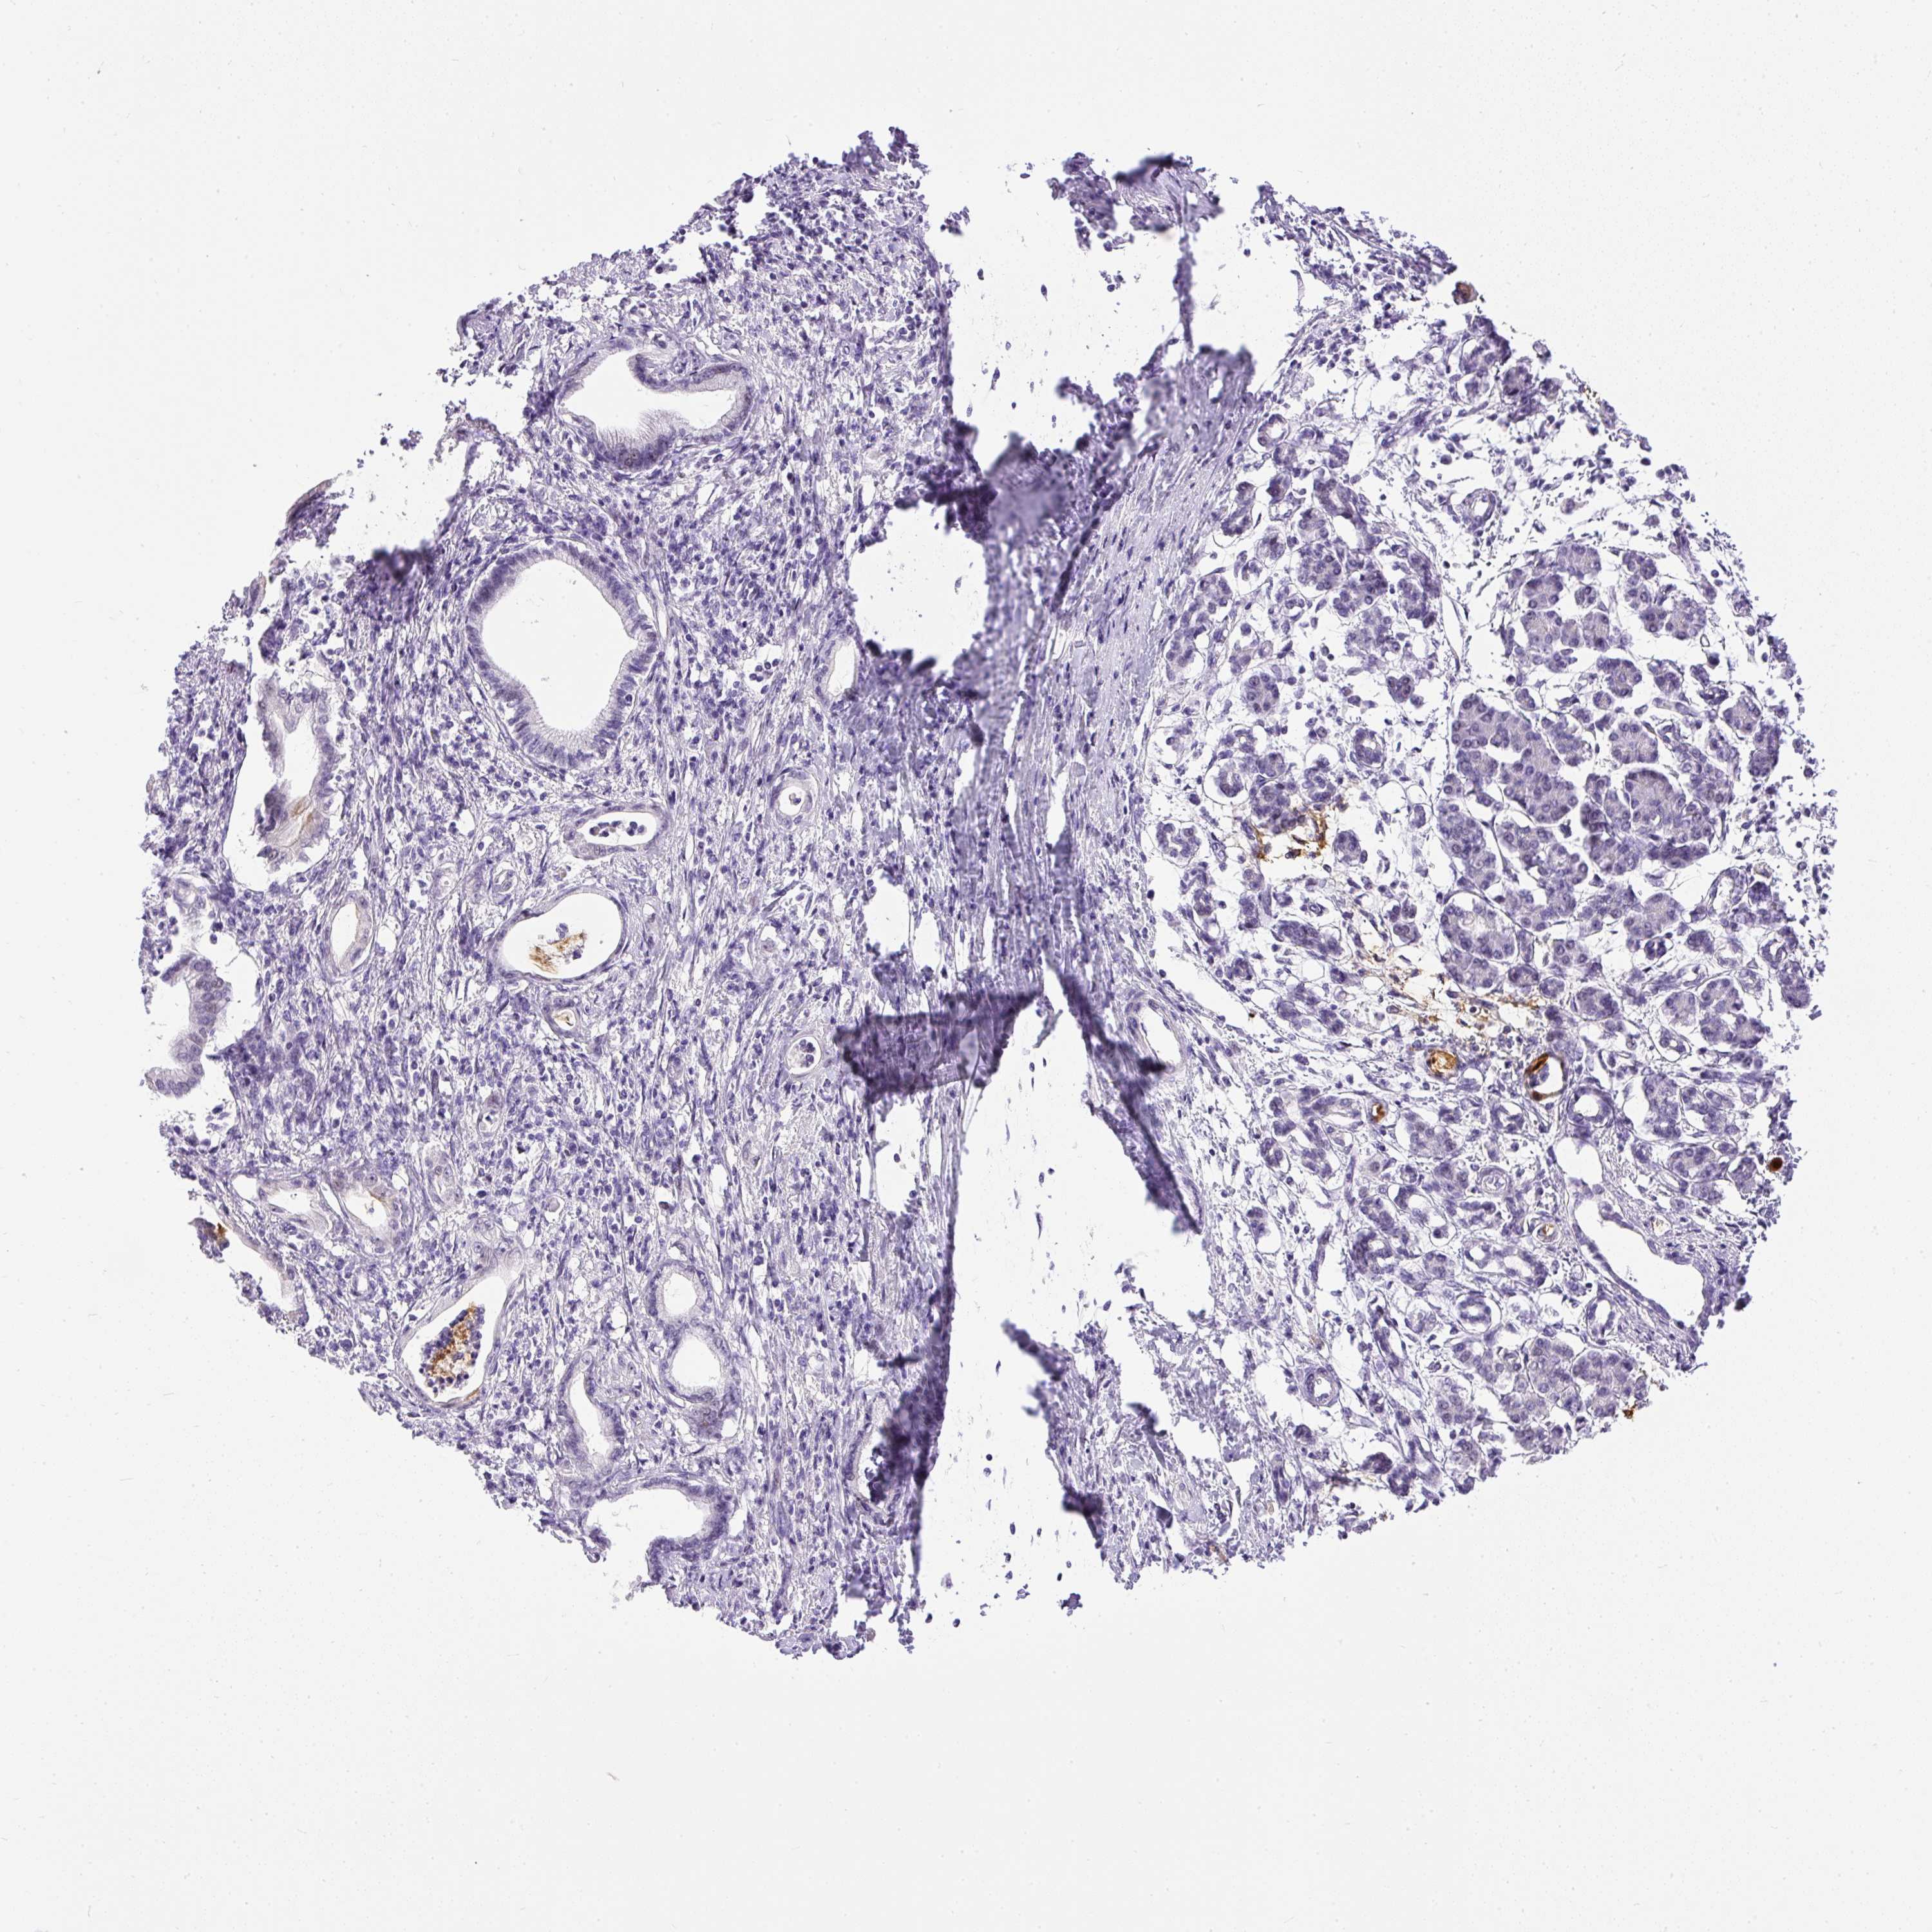

PANCREATIC CANCER - Protein expressioni

A mouse-over function shows sample information and annotation data. Click on an image to view it in a full screen mode. Samples can be filtered based on level of antibody staining by selecting one or several of the following categories: high, medium, low and not detected. The assay and annotation is described here.

Note that samples used for immunohistochemistry by the Human Protein Atlas do not correspond to samples in the TCGA dataset.

Antibody stainingi

Antibody staining in the annotated cell types in the current human tissue is reported as not detected, low, medium, or high, based on conventional immunohistochemistry profiling in selected tissues. This score is based on the combination of the staining intensity and fraction of stained cells.

Each image is clickable and will lead to virtual microscopy that enables deeper exploration of all samples and also displays staining intensity scores, fraction scores and subcellular localization as well as patient and tissue information for each sample.

Antibody HPA055048

Staining

High

Medium

Low

Not detected

Intensity

Strong

Moderate

Weak

Negative

Quantity

>75%

75%-25%

<25%

None

Location

Nuclear

Cytoplasmic/membranous

Cytoplasmic/membranous,nuclear

Adenocarcinoma, NOS